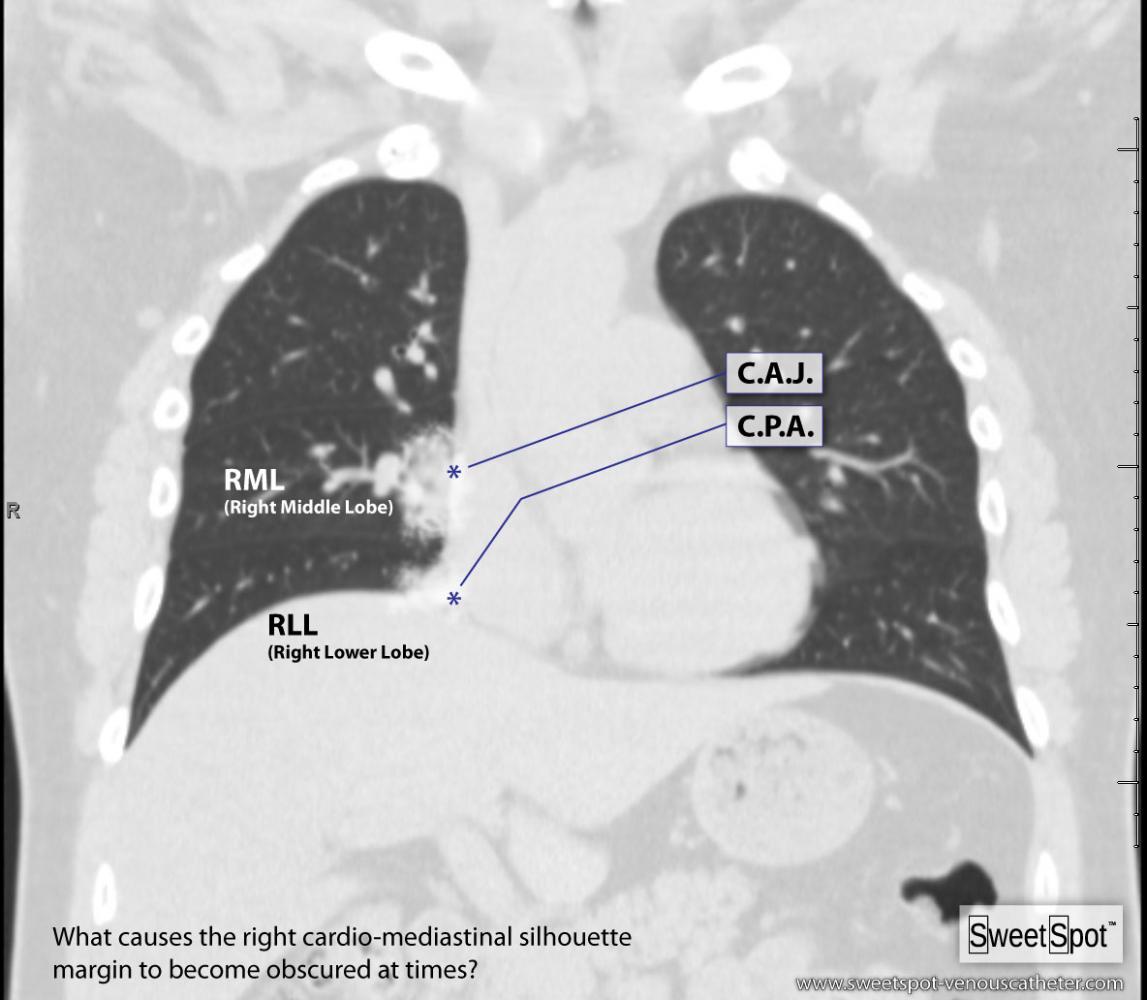

3. Chest x-ray rotation tissues: Not infrequently, the chest x-ray will be rotated causing the right cardiac margin to deviate from its normal AP appearance. In such situations, depending on the degree of rotation, an estimation of the SWEET SPOT™ is all that may be possible. In such circumstances, the right cardiophrenic angle is the most reliable anatomic landmark. Since the right atrium is immediately cephalad to a normally positioned right cardiophrenic angle, a reliable estimation of acceptable catheter tip location is still possible. The height, and consequently the width of the rectangular Sweet Spot™ box will be less exact and therefore a relatively short catheter tip position may require a non- rotated chest x-ray to confirm an acceptable location. Aim for the right atrium. See Figs. T.1, T.2, and T.3.

5. Abnormal appearance of the right cardiac border on non- rotated chest x-ray: Again, the cardiophrenic angle is the most reliable landmark and thus the same principles apply as in teaching point #3. See Fig.# 26 - Gallery.

6. Assessment of normal position of right cardiophrenic angle: The best way to confirm a normally positioned right cardiophrenic angle is to look at the left cardiophrenic angle. Generally speaking, the right cardiophrenic angle should be at approximately the same height as the left cardiophrenic angle. In the case of an elevated right cardiophrenic angle, experience and a solid understanding of SWEET SPOT™ anatomy may suffice. However with very low lung volumes and bilaterally raised hemi-diaphrams, even this may not be sufficient. See Fig. # 8.

15. The right margin of the high density cardiomediastinal silhouette is normally seen when low density aerated right lung is adjacent to it. Any process of soft tissue density that is situated at that margin will obscure that margin – proportional to its size. Common examples are pneumonia, atelectasis, tumor & pleural effusion. See Fig.# 26 - Gallery. Also see slide #46 of AVA Presentation.